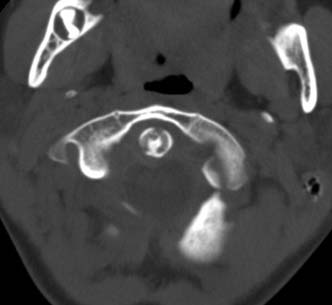

标题: PED0678:男,10岁,寰枢椎平扫。 [打印本页]

标题: PED0678:男,10岁,寰枢椎平扫。

患者在校与同龄孩子打闹后(据家长说被拳击中颈部)出现颈部不适30分钟后入院检查,来时脖子歪斜。请大家看看枢椎齿状突及寰枢关节有问题吗?(3mm层厚断层扫描)。